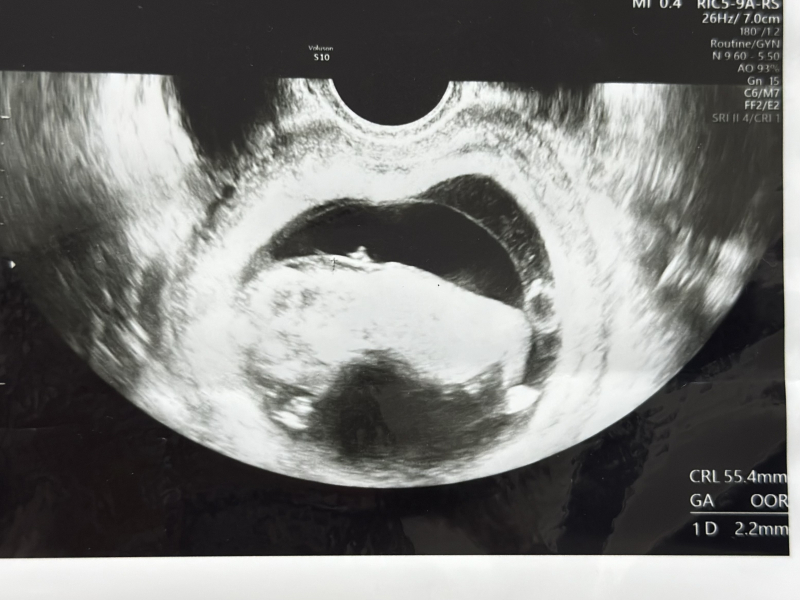

NT 首の後ろの厚さ

首の後ろの厚さが2.2mm、2.5mmが正常値なので、正常値内ですけど、少し厚い方ですね。羊水検査をしますか?

調べても2.2mmは正常値内としか出て来ません。

首の後ろの厚みについて、先生から少し厚みがあるということで、羊水検査を希望されるかお話があったのですね。

書かれていたように、正常範囲内であるように思います。